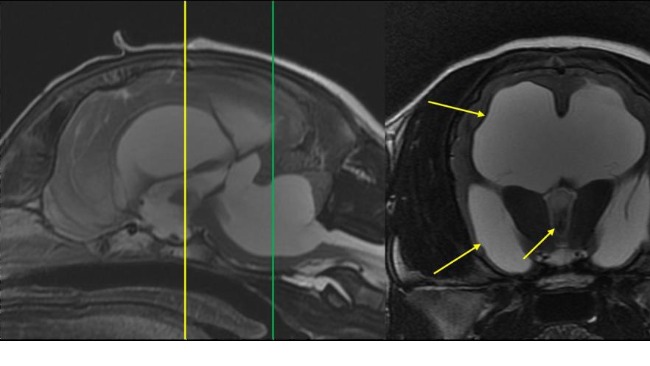

Po wizycie u neurochirurga i wykonaniu rezonansu stan szczeniaka spowodowany jest nagromadzeniem się płynu w czaszce, który uciska na nerwy powodując ból. Prościej choruje na wodogłowie.

Wstawiam Wam zdjęcia z prześwietlenia i opis.

Ten biały obszar który widać na zdjęciu to płyn, a czarny to mózg który jest uciskany.